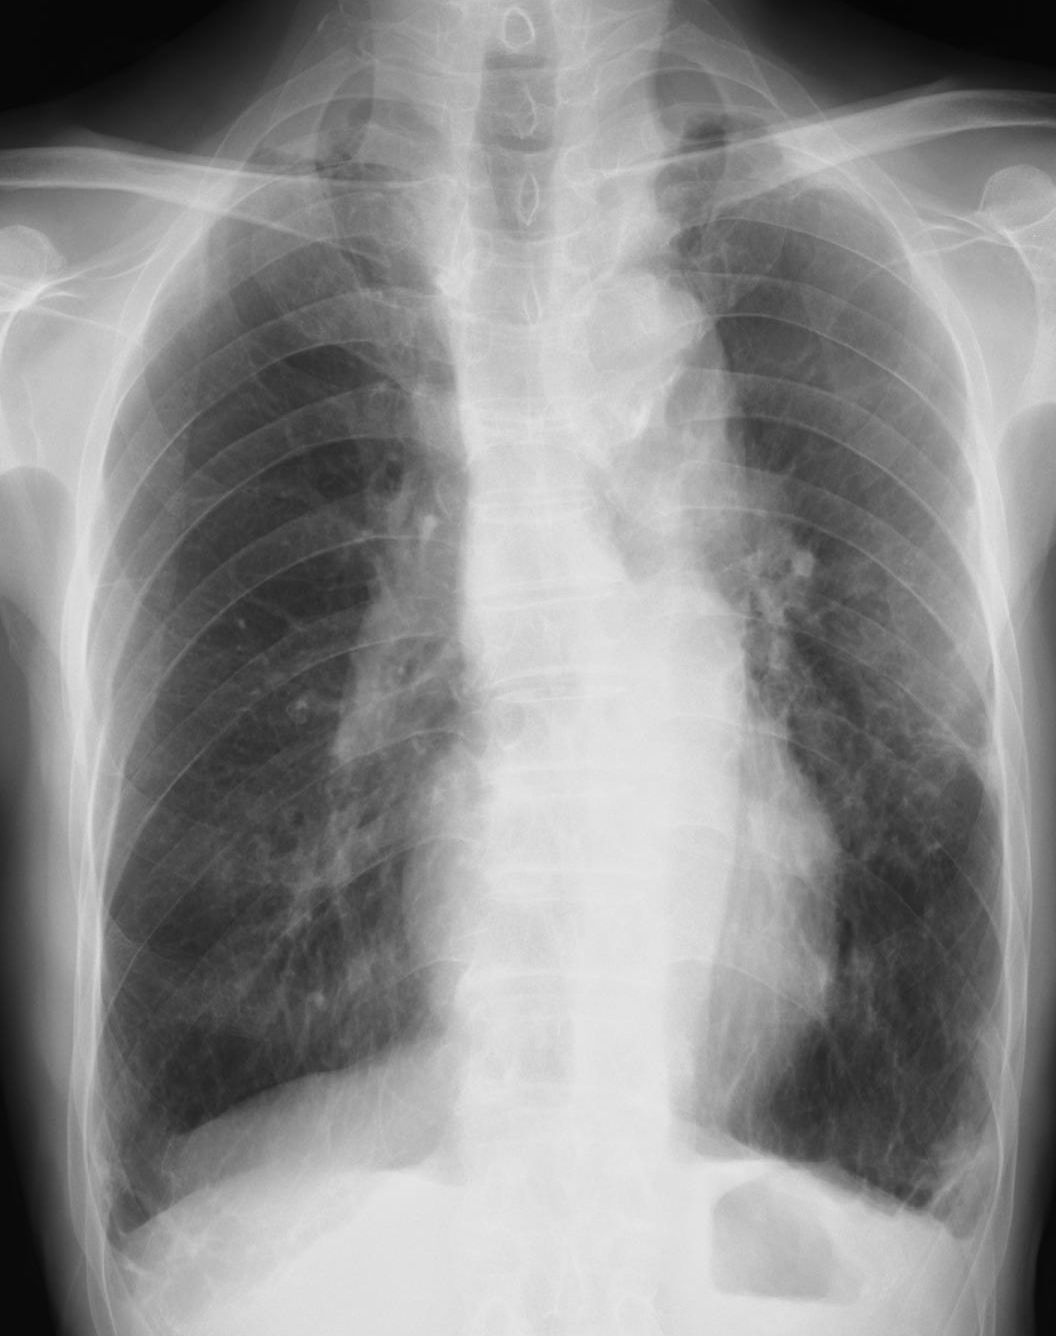

[注意] 心陰影にみえる肺門陰影(右)、シルエットサイン陰性に気づけば肺炎像と理解できる。また、左肺門部陰影は心辺縁が不鮮明(シルエットサイン陽性)で同部にも浸潤影があることが推定できる。 肺門部の浸潤影はいつも慎重に判断する必要がある。下写真の左肺門部の心陰影ははっきりせず(左上挿入写真は治癒時)判断に迷うがシルエット陽性と判断すればS6もしくはS3の肺炎が推定可能になる。下の写真はS6の浸潤影が想定される。 [肺門の陰影]

左は肺門の変化からマイコプラズマ肺炎と診断、オゼックス投与にて解熱しないため3日後に確認したところ浸潤影が拡大していた。 [心陰影の把握]